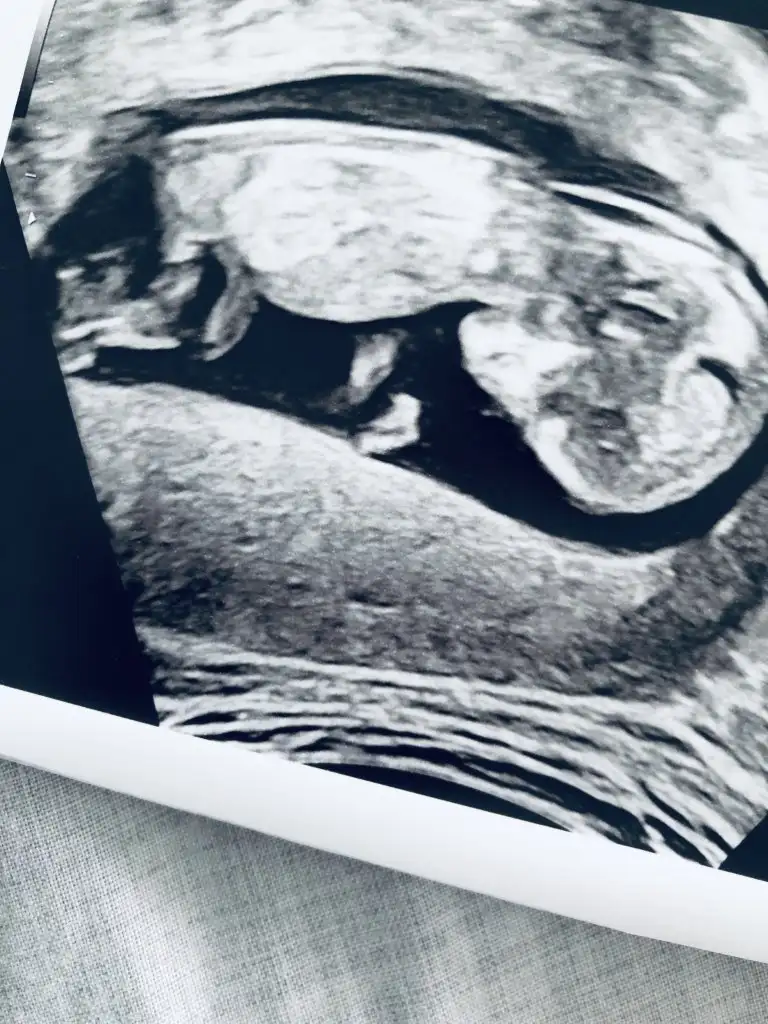

Erkek gibiTahmin edebilcek olan var mı lütfen dr söyledi 12. Haftada bakalım aynı mı

Kız gibi gibi nubu çok karışık çıkmış 11 haftasu varmı usgniz 12+6 öncesi varsa paylaşırmısınızTahmin :)

Ay bilemedimki 10 dkk baktım nubu çok karışık çıkmış kararımı kıza kullandımAy yok ki bi 6. Haftada gittim bidaha 12. Haftada:)

Net miErkek gibi

Hahaha teşekkür ederim hayırlısı inşallah:)Ay bilemedimki 10 dkk baktım nubu çok karışık çıkmış kararımı kıza kullandım

Yani dr daha detaylı bakıyor ilk bebekmi gönlünüzdeki saglıkla nasip olsunNet mi ☺

Ay hadi hayırlısı olsun bakalım arka sayfalarda bir iki tane daha attığım vardı ikra ile videoyu falanda baya inceledik ama tam net değildi erkeğe daha yakındı bakalım ne çıkacak yavru kuş

16 degil 11 -12 yada 13 haftalar olmalı dr söylemedimi sanki erkek gibi ama dediğim haftalara tahmin ediyorum